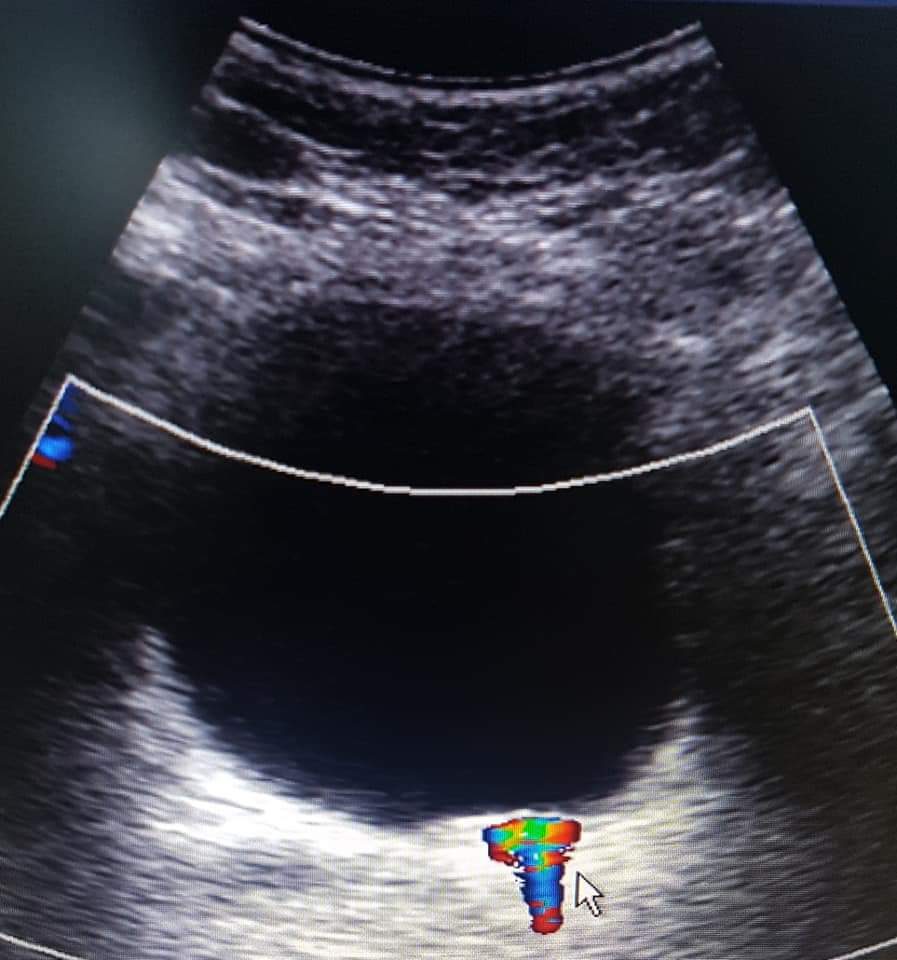

En las imágenes mostramos el caso de un lito (piedra) atorado en la porción más distal del ureter izquierdo cercano a su unión con la vejiga. El diagnóstico se realizó mediante ultrasonido.

Dra. Alejandra Espinoza

Especialista en Radiología.